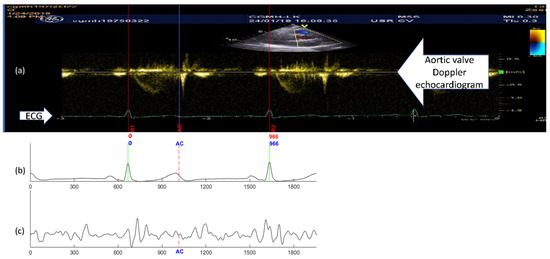

The DTW-base quasi-synchronous alignment introduces two modifications to the conventional quasi-synchronous alignment: (1) the intermediary reference signal pair, and (2) DTW-based point-to-point alignment of two signal sequences. The examples and comparison of SCG fiducial point detections in the nonreference SCG signal using the conventional and DTW-based quasi-synchronous alignment methods are demonstrated in Figure 7. Figure 7a–c illustrate the conventional approach, whereas Figure 7d–g display the DTW-based approach. The echocardiogram shown in Figure 7a is a color Doppler flow measurement at the aortic valve. In Figure 7a, the 966-ms period between R1 and R2 is selected as the synchronization target. The signals in Figure 7b,d represent the same nonreference ECG signal, whereas Figure 7b is rescaled (squeezed to fit signal length of 1003 ms to 966 ms) and shifted such that it can be visually aligned to the ECG R1-R2 section in Figure 7a. The signals in Figure 7c,f represent the same SCG signal (other than the reference SCG signal). Figure 7c has been rescaled and synchronized to Figure 7b.

2.5.1. Common Procedures under Both Alignment Methods

An RR interval in the echocardiogram image was selected and the ends were annotated as R1 and R2. A visually recognized AC event was marked by a blue line and labeled as “AC” in the echocardiogram (Figure 7a). The present RR interval (966 ms) was obtained by pixel counting from the timing ticks in the echocardiogram.

2.5.2. Conventional Quasi-Synchronous Alignment

The SCG and ECG signals were shifted and rescaled to align R peaks to R1 and R2 in the ECG of echocardiogram (Figure 7a–c). The fiducial point was obtained by extending the blue line from Figure 7a–c.

2.5.3. DTW-Based Quasi-Synchronous Alignment

A reference signal pair of ECG and SCG was sorted out with the RR interval closest to the R1–R2 period. In this example, the reference signal pair had a heartbeat cycle of 966 ms. Shifting, but not rescaling, was required to align the reference signals until the ECG R peaks matched R1 and R2, as shown in Figure 7e,g. Referring to the condition in Figure 4, the ECG signals in Figure 7a,e, as well as the echocardiogram and SCG signal in Figure 7g, are postulated to align to each other (within the RR interval) spontaneously. The fiducial point AC was detected in the reference SCG signal by extending the blue line from Figure 7a–g. The fiducial point AC was projected from the reference SCG signal (Figure 7g) to nonreference SCG signal (Figure 7f) with the aid of a DTW-based software program, as shown in Figure 7f–i.

As mentioned earlier, a fiducial point detection error resulted from the signal rescaling manipulation in the conventional quasi-synchronous alignment, as indicated by the width of the yellow rectangle in Figure 7h. Figure 7i displays the results of DTW point-to-point alignment with the new cost function between the reference SCG signal (red) and the target nonreference signal (blue).

Figure 7. Illustrations and comparison of the fiducial point detection in the nonreference SCG signal between the methods of the conventional and the DTW-based quasi-synchronous alignment: (a) Doppler echocardiogram image with the identified ECG R peaks (R1, R2) and aortic valve closing (AC) event; (b) ECG alignment (to the ECG signal in the echocardiogram) under the conventional quasi-synchronization (aligned through shifting and rescaling); (c) SCG signal (synchronous to (b)) aligned by the conventional approach with the fiducial point AC detected by virtual line extending from the echocardiogram; (d) Nonreference ECG signal (no need for R peaks alignment to other ECG signal); (e) Reference ECG signal with R peaks aligned to ECG R peaks in the echocardiogram R1 and R2 (aligned by shifting only) under DTW-based quasi-synchronous alignment; (f) Nonreference SCG signal (synchronous to (d)) with the fiducial point AC projected by DTW-based quasi-synchronous alignment; (g) Reference SCG signal (synchronous to (e)) aligned to echocardiogram with the fiducial point AC detected by virtual line extending from the echocardiogram under DTW-based approach; (h) The detection error (indicated by the width of yellow rectangle in the upper graph) of the conventional method illustrated by comparing the AC points detected from conventional quasi-synchronous alignment (upper trace) and DTW-based (middle trace) approach; (i) Point-to-point mapping of the nonreference SCG signal (upper trace) with the reference SCG signal (lower trace) under DTW alignment.